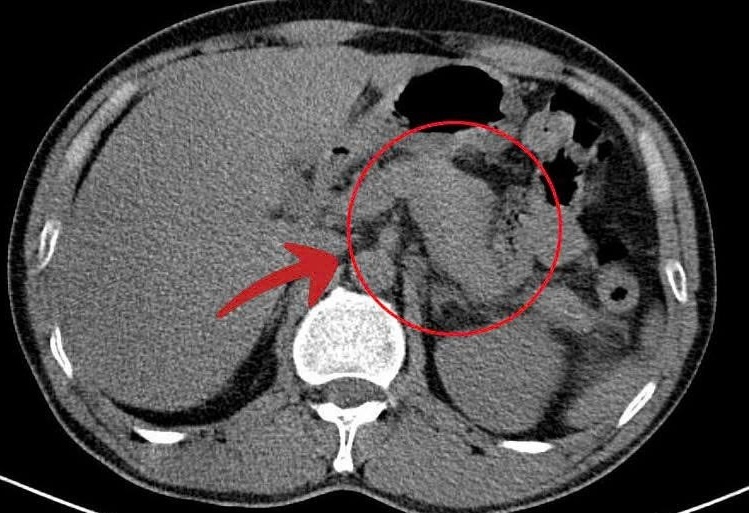

Sốt rét ác tính có thể ảnh hưởng đến nhiều cơ quan như não, gan, lách, thận, tim, phổi... gây giảm cung cấp máu và thiếu oxy. Đây là tình trạng có tỷ lệ nguy hiểm tính mạng cao, phụ thuộc vào loài ký sinh trùng, yếu tố cá nhân và thời điểm được cấp cứu điều trị. Vì vậy, việc đưa bệnh nhân đến cơ sở y tế sớm rất quan trọng nhằm ngăn chặn biến chứng nguy hiểm và nâng cao hiệu quả điều trị.

• Tổn thương phủ tạng: suy thận cấp, viêm gan, suy gan, phù phổi cấp, rối loạn tim mạch, choáng.

Các thể lâm sàng có thể gặp: suy tuần hoàn cấp, thể bụng cấp, suy gan cấp, suy thận cấp, phù phổi cấp, hội chứng suy hô hấp tiến triển, xuất huyết - đông máu rải rác, thể tiểu huyết cầu tố.